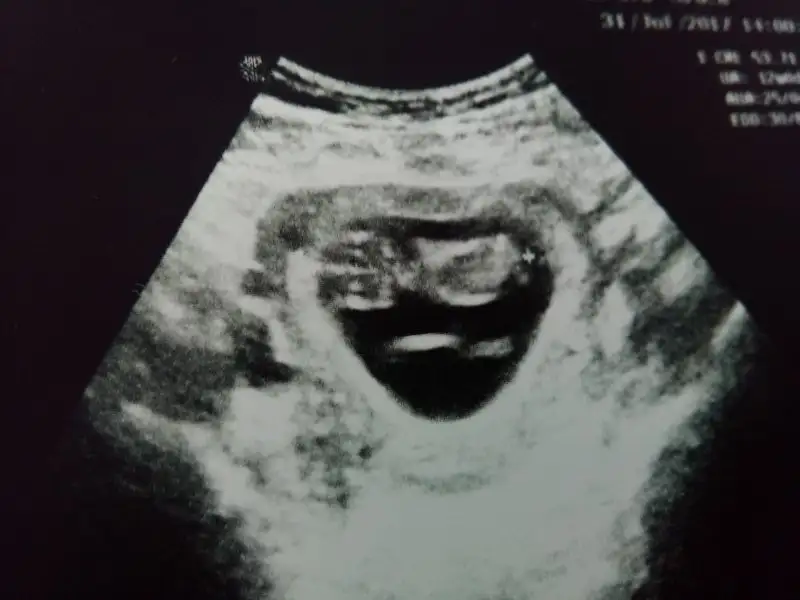

Kızlar kızlar yakından cektim bir daha bi baksanız benim minnak kuzuya :))

Eklentiler

• IMG_20170801113253.webp

14,9 KB · Görüntüleme: 93

Buda kalp atış hızı sanırım ben öyle tahmin ettim 53.71 mm olmuş boyu kızlar sizce normal mi sizlerin nasıl

• IMG_20170801113300.webp

13,6 KB · Görüntüleme: 79